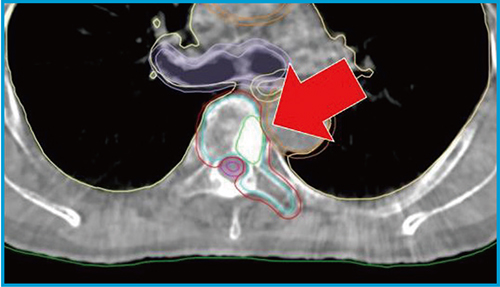

2.椎体定位照射

次に,椎体定位照射に対してHyperSight CBCTを適応した。高分解能により標的となる椎体内の肉眼的腫瘍体積(GTV)の視認が容易となり,リスク臓器である脊髄の観察も行えるようになったことで,より高精度な画像位置照合精度が担保される。今後,セットアップマージン縮小の再考を行う予定である。

図2に,実際の HyperSight CBCTを示す。←で示したGTV(緑色のライン)が鮮明に視認可能であることがわかる。

図2 椎体定位照射におけるHyperSight CBCT画像

(ストラクチャー含む,GTV=緑色のライン)